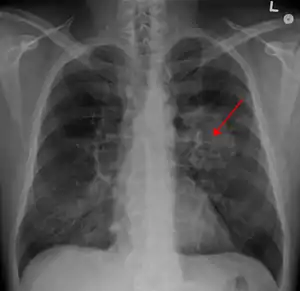

![]() Tumoare pulmonară (marcată cu săgeată) vizibilă la radiografia toracică | |

Efectuarea unei radiografii toracice reprezintă unul dintre primii pași necesari pentru a investiga dacă o persoană prezintă simptome care pot sugera prezența cancerului pulmonar. Această radiografie poate arăta o masă evidentă, o extindere a mediastinului (sugerează răspândirea în nodulii limfatici), atelectazie (colabare), consolidare (pneumonie) sau revărsat pleural.[5] Imagistica prin computer tomograf este de obicei folosită pentru a oferi mai multe informații cu privire la tipul și gradul de extindere al bolii. Bronhoscopia sau biopsia ghidată CT este adesea folosită pentru a preleva mostre din tumoare pentru histopatologie.[13]

Cancerul pulmonar se prezintă, de cele mai multe ori, ca un nodul pulmonar solitar în cadrul unei radiografii toracice. Cu toate acestea, diagnosticul diferențial este extins. Multe alte boli pot să prezinte aceleași simptome, inclusiv tuberculoza, infecțiile fungice, cancerul metastatic sau pneumonia organizată. Printre cauzele mai puțin comune ale nodulului pulmonar solitar se numără hamartomul, chisturile bronhogenice, adenoamele, malformația arterio-venoasă, sechestrarea pulmonară, nodulii reumatoizi, granulomatoza Wegener sau limfomul.[45] Cancerul pulmonar poate fi, de asemenea, descoperit incidental, sub forma unui nodul pulmonar solitar la nivelul unei radiografii toracice sau tomografii computerizate realizate din alte motive.[46] Diagnosticul definitiv de cancer pulmonar are la bază examinarea histologică a țesutului suspectat în context clinic și radiologic.[4]